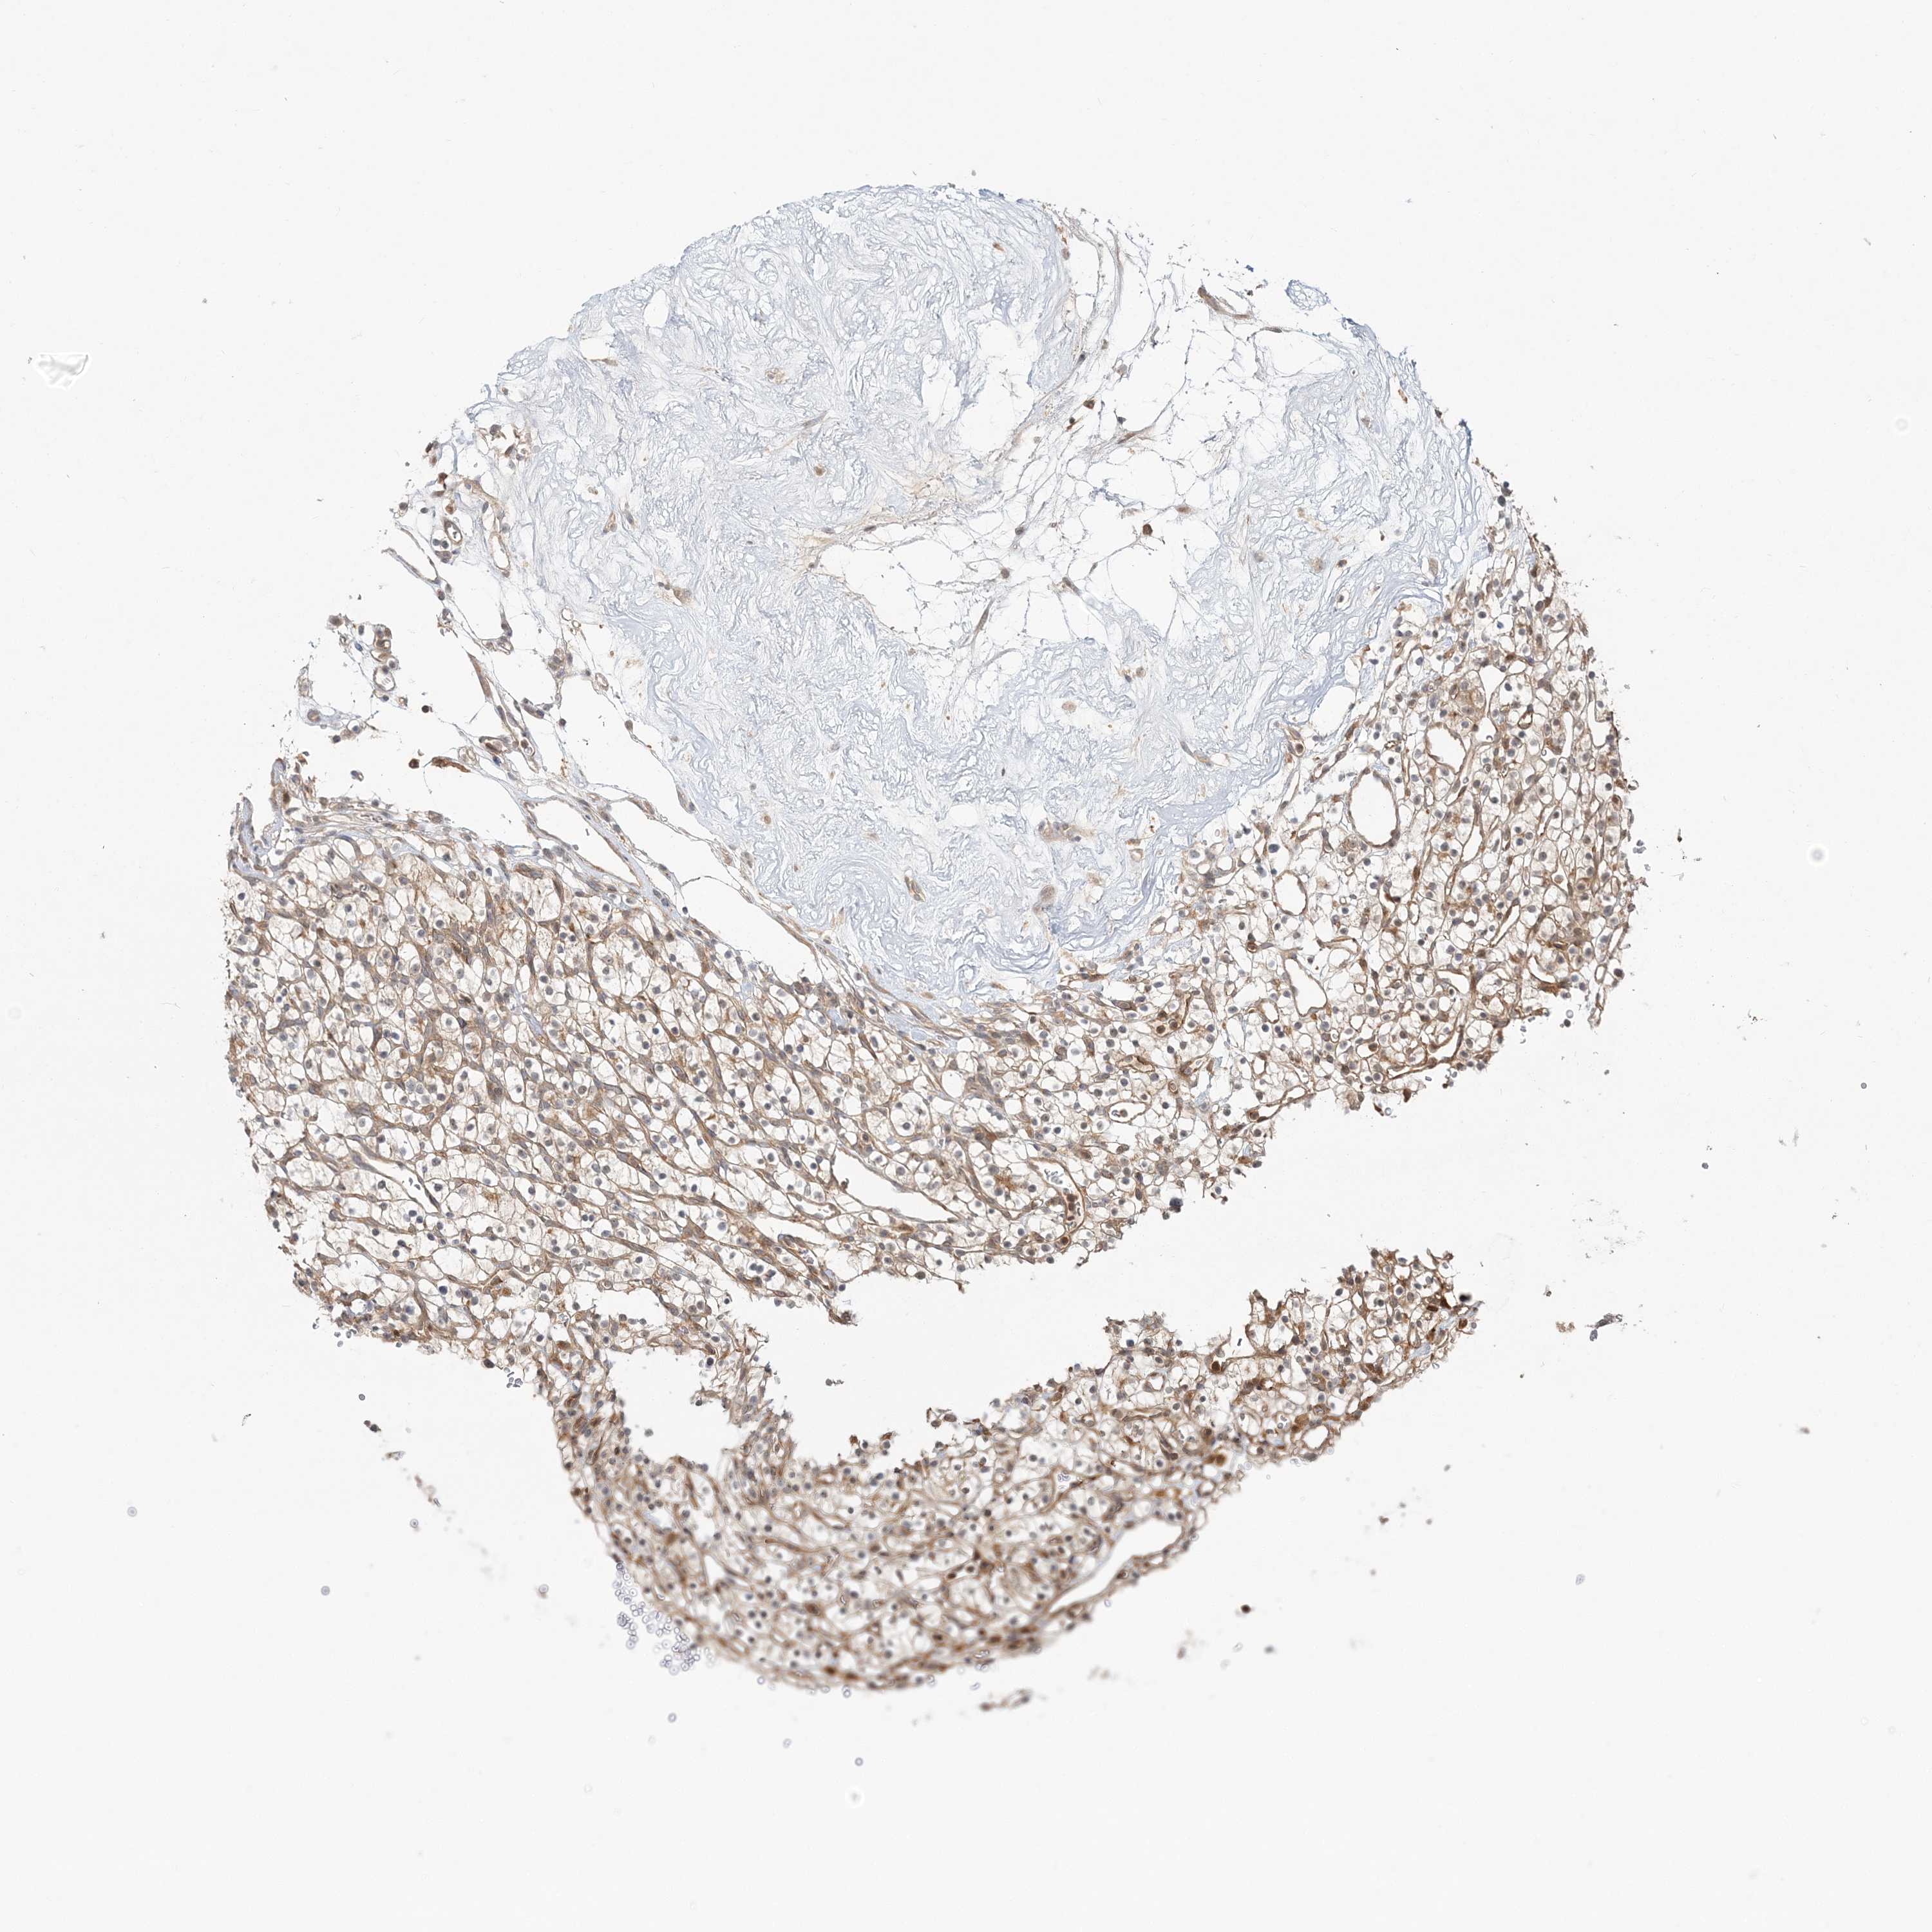

KIDNEY RENAL CLEAR CELL CARCINOMA (VALIDATION) - Interactive survival scatter ploti

The Survival Scatter plot shows the clinical status (i.e. dead or alive) for all individuals in the patient cohort, based on the same data that underlies the corresponding Kaplan-Meier plots. Patients that are alive at last time for follow-up are shown in blue and patients who have died during the study are shown in red.

The x-axis shows the expression levels (FPKM) of the investigated gene in the tumor tissue at the time of diagnosis. The y-axis shows the follow-up time after diagnosis (years). Both axes are complimented with kernel density curves demonstrating the data density over the axes. The top density plot shows the expression levels (FPKM) distribution among dead (red) and alive patients (blue). The right density plot shows the data density of the survived years of dead patients with high and low expression levels respectively, stratified using the cutoff indicated by the vertical dashed line through the Survival Scatter plot. This cutoff is automatically defined based on the FPKM cutoff that minimizes the p-score. The cutoff can be changed by dragging the vertical line or by entering a cutoff value in the square labeled "Current cut-off".

Under the Survival Scatter plot the p-score landscape (black curve; left axis) is shown together with dead median separation (red curve; right axis). Dead median separation is the difference in median mRNA expression between patients who have died with high and low expression, respectively. It is calculated as follows: median FPKM expression of dead patients with high expression - median FPKM expression of dead patients with low expression. This is intended to aid the user in visually exploring custom cutoffs and the associated p-scores and dead median separation.

Individual patient data is displayed and can be filtered by clicking on one or more of the category buttons on the top of the page. Categories describing expression level and patient information include: high, low, alive, dead, female, male and tumor stages. The scale of the x-axis can be toggled between linear and log-scale by clicking on the "x log" button. Mouse-over function shows TCGA ID, patient information and mRNA expression (FPKM) for each patient.

& Survival analysisi

Kaplan-Meier plots summarize results from analysis of correlation between mRNA expression level and patient survival. Patients were divided based on level of expression into one of the two groups "low" (under cut off) or "high" (over cut off). X-axis shows time for survival (years) and y-axis shows the probability of survival, where 1.0 corresponds to 100 percent.

CAB39 is not prognostic in Kidney Renal Clear Cell Carcinoma (validation)

Best expression cut offi

Based on the FPKM value of each gene, patients were classified into two groups and association between prognosis (survival) and gene expression (FPKM) was examined. The best expression cut-off refers the FPKM value that yields maximal difference with regard to survival between the two groups at the lowest log-rank P-value. Best expression cut-off was selected based on survival analysis .

When clicking on this number, the vertical dashed line indicating cut-off, the interactive survival plot, and the Kaplan-Meier curve will be adjusted to show results based on the best expression cut-off.

: 36.43

P scorei

Log-rank P value for Kaplan-Meier plot showing results from analysis of correlation between mRNA expression level and patient survival.

N/A

TCGA RNA samplesi

RNA-seq data is reported as average FPKM (number Fragments Per Kilobase of exon per Million reads), generated by the The Cancer Genome Atlas (TCGA) .

Normal distribution across the dataset is visualized with box plots, shown as median and 25th and 75th percentiles. Points are displayed as outliers if they are above or below 1.5 times the interquartile range. FPKM values of the individual samples are presented next to the box plot.

Average pTPM 48.6

Number of samples 100